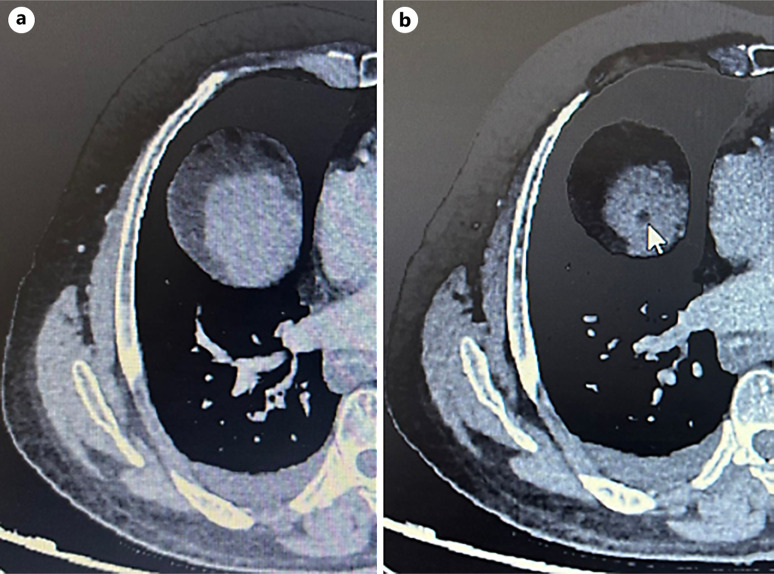

Case presentation: A 63-year-old male with compensated hepatitis B-related cirrhosis was under routine surveillance when a suspicious liver lesion was detected on ultrasound. Subsequent contrast-enhanced computed tomography (CT) confirmed the presence of an 18-mm HCC in segment VIII, corresponding to Barcelona Clinical Liver Cancer stage A. Due to limited curative treatment options, transarterial chemoembolization was considered. However, a follow-up CT scan was performed 2 weeks before the procedure unexpectedly revealed complete regression of arterial enhancement, suggestive of spontaneous tumor necrosis. The patient remained asymptomatic, with stable liver function and mild biological inflammatory markers. No evidence of vascular thrombosis or significant systemic inflammation was noted, suggesting localized vascular disturbances or intrinsic tumor factors might have precipitated the necrosis.